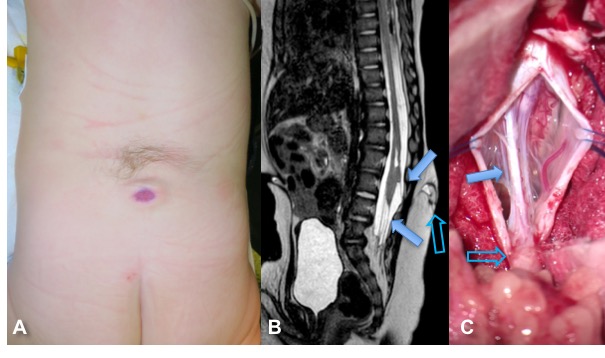

la méningocèle manquée

(manquée comme un soufflé qui n’est pas monté) elle comporte tous les éléments de la méningocèle (anomalie cutanée atrophique, tractus sous-jacent jusqu’à la dure-mère et la moelle, moelle basse) mais pas de poche liquidienne sous-cutanée. la chirurgie a pour but de défixer la moelle, en sectionnant le tractus à ras du cordon médullaire, ainsi que le filum terminale qui est souvent dysplasique.

limited dorsal myeloschisis lombaire